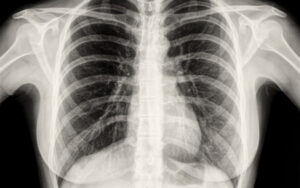

Флюорография при грудном вскармливании: за и против

Флюорография — это диагностический тест, направленный на выявление первых симптомов респираторных заболеваний: пневмонии, туберкулеза, кистозной гиперплазии и злокачественных новообразований. При подозрении на патологию (после флюорографии) пациента направляют на дополнительное обследование — рентген легких. Различия между этими методами. Принцип действия этих методов основан на рентгеновских лучах, только в первом случае доза в несколько раз ниже. Информативное …